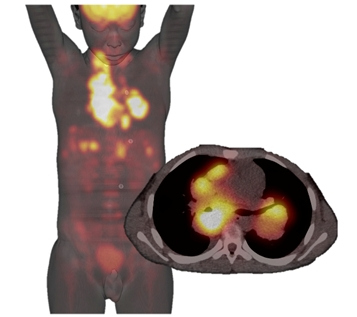

En LNH difuso de células B grandes y los linfomas foliculares de grado 2 ó 3 demostraron el más alto metabolismo para la captación del FDG (fig. 3). Esto normalmente se traduce en un Valor Estándar de Captación (SUV) tres veces mayor que en un folicular de bajo grado, la zona marginal, o linfoma de células pequeñas, en la que el SUV tiende a ser más bajo31. Para el LH, al menos, algunos autores han demostrado una diferencia significativa en la avidez por la FDG entre los subtipos histológicos, siendo el subtipo de Esclerosis Nodular (EN) el que tiene más alto SUV y el subtipo de Predominio Linfocitario con el menor SUV.